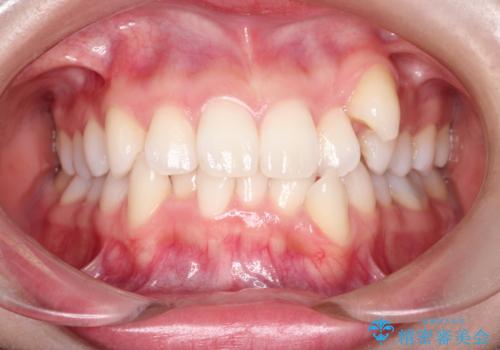

【審美ワイヤー】八重歯を治したい。

- 20代女性

- 左上の犬歯の凸凹や正中のずれを主訴に来院されました。

凸凹を治すために、上下左右の小臼歯を抜歯してワイヤー矯正を行いました。

患者様には、顎間ゴムを使用していただくことで、2年という期間で治療を終了することができました。